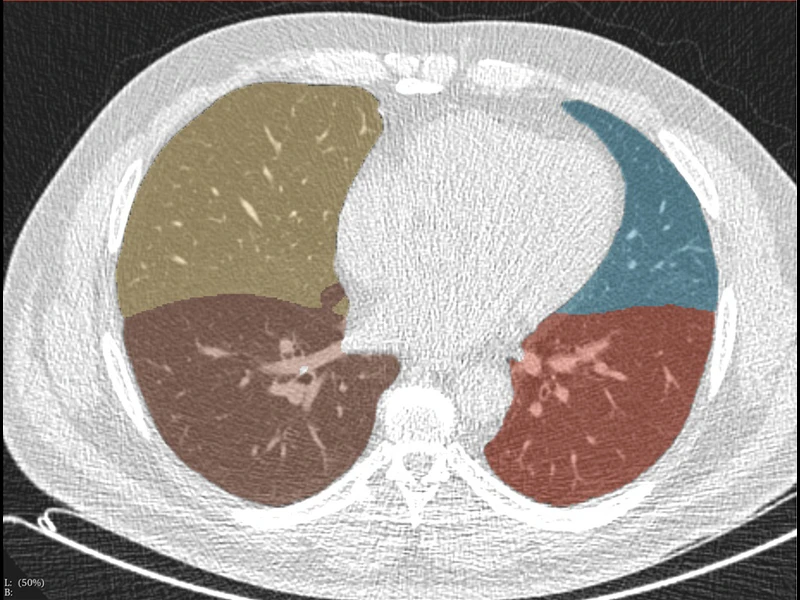

AIRS can also be applied to LDCT scans for disease assessments beyond lung cancer, as described in the Journal of Thoracic Imaging paper.

Other AI-enabled applications from a single low-dose chest scan include muscle and fat distributions, alcoholic liver disease, nonalcoholic liver disease, hepatic cancers, metabolic disorders, and pancreatic and kidney cancers. Pancreatic cancer is more deadly than lung cancer, but early detection has been shown to greatly increase survival.